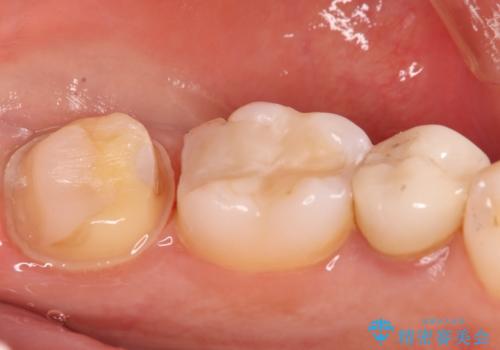

- 奥歯に虫歯があると言われて治療された患者様です。

何度か同じ歯に保険治療で治したそうですが、欠けたり再度う蝕になってしまった経験から自費治療を希望され、丈夫でキレイなセラミッククラウンにて治療いたしました。